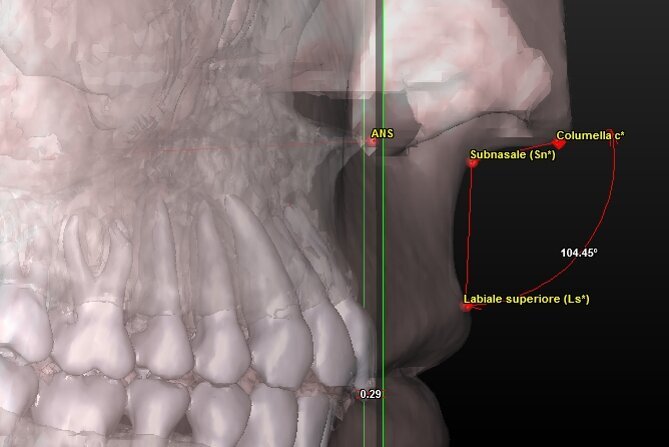

| Punto A |

Punto più arretrato della concavità del mascellare superiore tra ANS e la cresta alveolare. |

| ANS (Anterior Nasal Spine) |

Punto più avanzato del profilo del mascellare superiore a livello della sutura palatina mediana. |

Componente dentale (Tab. 4) (Figg. 8, 9):

Angolo tra asse spinale e asse incisale |

| Posizione Incisale (UIm – ATP) |

mm |

da ricercare |

Distanza tra UIm e l’Anterior Facial Plane |

Fig. 8_Valutazione della componente dentale in visione para-frontale.

Fig. 9_Valutazione della componente dentale in visione di profilo.